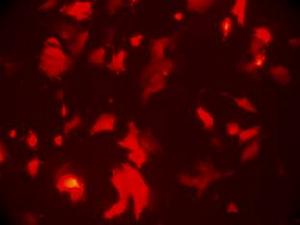

腺病毒感染確診較難,須做病原學及血清學檢查,取病人鼻咽部脫落細胞塗片,用帶有螢光素的多價腺病毒抗體染色,可見細胞核內有螢光,可藉此快速診斷。亦可取鼻、咽及結膜分泌物做病毒分離或用急性期及恢復期雙份血清做補體結合試驗、血凝抑制試驗和中和試驗。